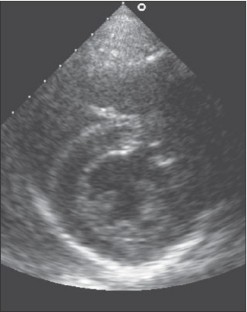

Cardiac remodelling is commonly defined as a physiological or pathological state that may occur after conditions such as myocardial infarction, pressure overload, idiopathic dilated cardiomyopathy or volume overload. When training excessively, the heart develops several myocardial adaptations causing a physiological state of cardiac remodelling. These morphological changes depend on the kind of training and are clinically characterised by modifications in cardiac size and shape due to increased load. Several studies have investigated morphological differences in the athlete’s heart between athletes performing strength training and athletes performing endurance training. Endurance training is associated with an increased cardiac output and volume load on the left and right ventricles, causing the endurance-trained heart to generate a mild to moderate dilatation of the left ventricle combined with a mild to moderate increase in left ventricular wall thickness. Strength training is characterised by an elevation of both systolic and diastolic blood pressure. This pressure overload causes an increase in left ventricular wall thickness. This may or may not be accompanied by a slight raise in the left ventricular volume. However, the development of an endurancetrained heart and a strength-trained heart should not be considered an absolute concept. Both forms of training cause specific morphological changes in the heart, dependent on the type of sport. (Neth Heart J 2008;16:129-33.)